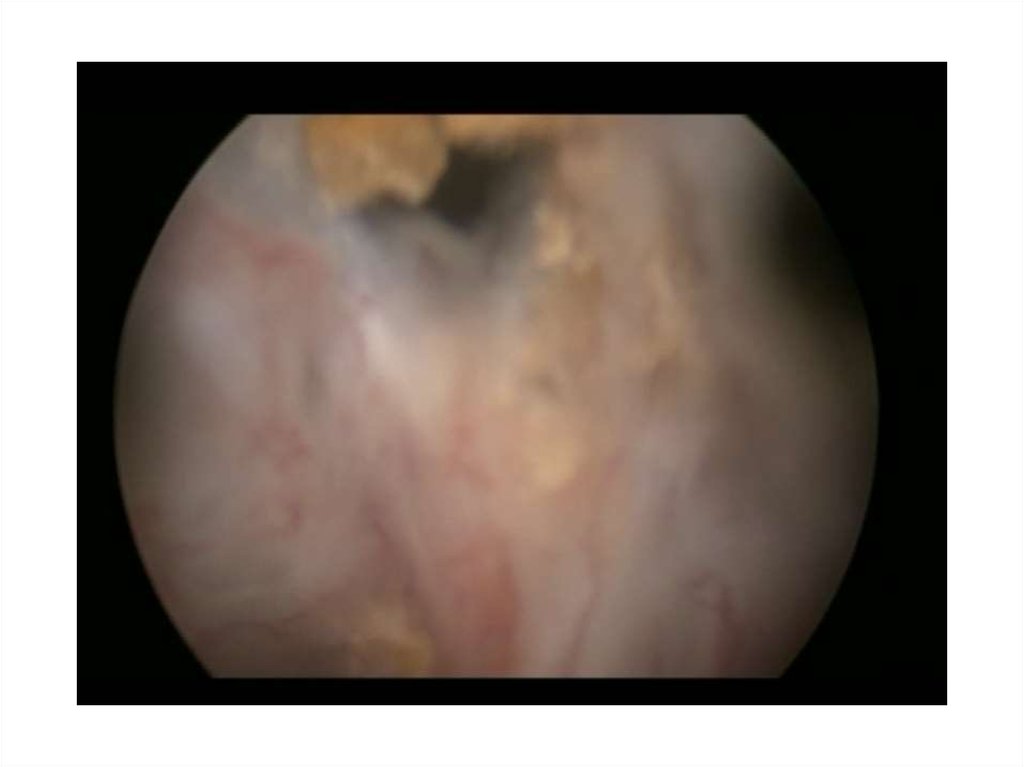

8. Кузнецов В.А. 59лет

• 13.11.14 – лазерная энуклеация ГПЖ

• 26.10.15 – ТУР шейки мочевого пузыря

• С января 2016 года отмечает ухудшение

качества мочеиспускания